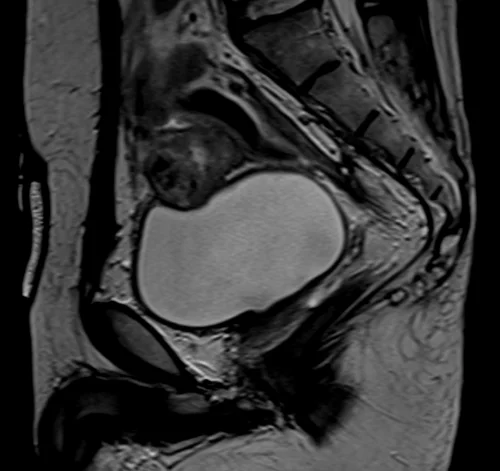

mri urinary bladder sagittal t2 image 2 - MRI